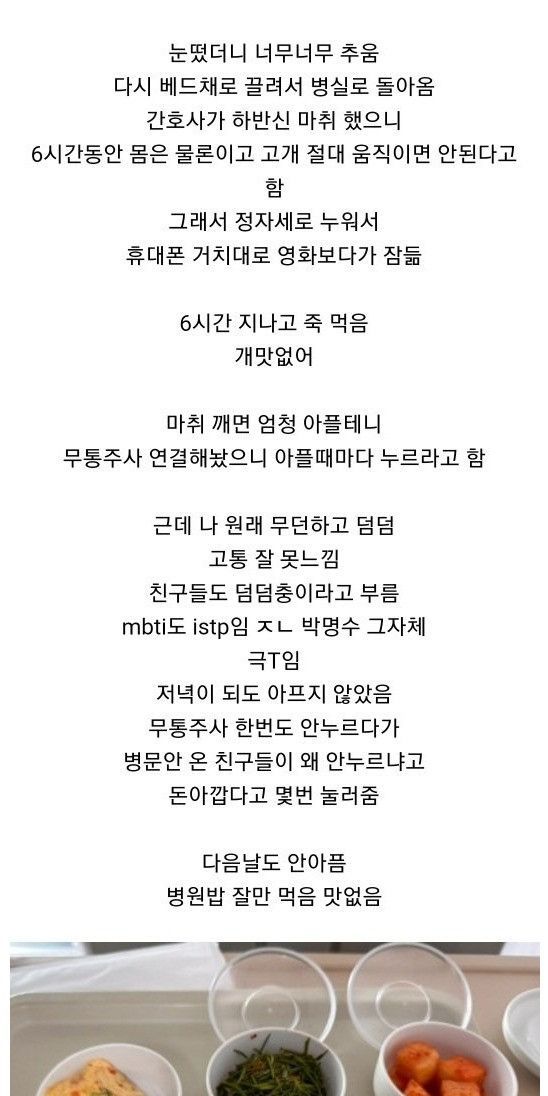

빙판길에서 자빠져 발목 부러져서 수술

수술했는데 하나도 안아픔